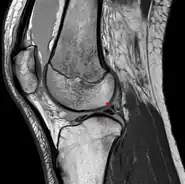

Posterior meniscofemoral ligament on MRI, coronal